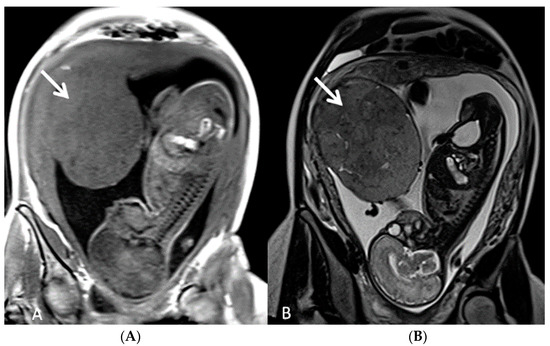

3.1.5. Placental Mesenchymal Dysplasia

3.1.6. Chorioangioma